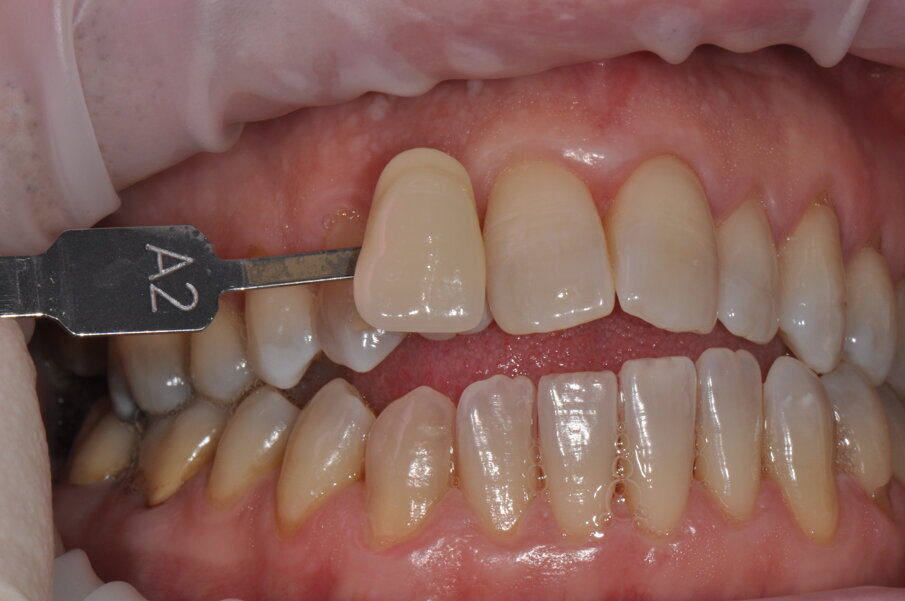

Fig. 1 - Fotografia frontale scattata prima della seduta di igiene professionale (Guided Biofilm Therapy) rilevazione del colore a tempo zero, utilizzando la scala colore “Vita”.

Fig. 8 - Rilevamento del colore a tempo zero utilizzando la scala “Vita” D3.